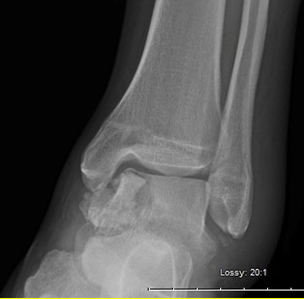

This is a AP view of a painful ankle, Left foot.